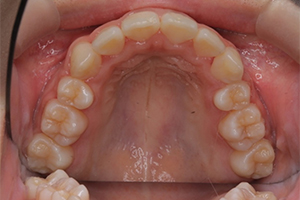

矯正治療のCASE 02

Before

After

- 主訴

- 上顎前歯が出ていて口が閉じにくい

- 治療内容

- 上顎前突・出っ歯の非抜歯による歯並び治療

- 治療費用

- 88万円~(税込)

- 治療期間

- 12ヶ月

【リスク・副作用】

歯の痛み、口内炎、歯磨きがしにくいことによるむし歯や歯周病のリスク、歯根吸収や歯の変色、後戻りなどの副作用があります。